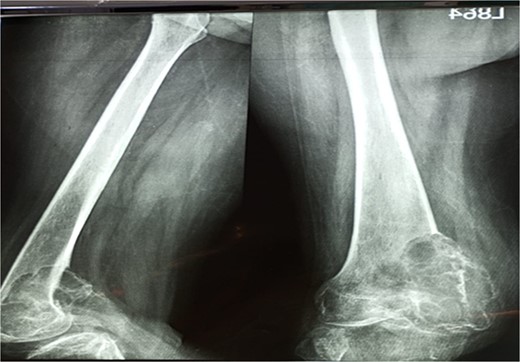

A 28-year-old female patient in her first trimester of pregnancy presented in our outpatient department with a complaint of persistent left knee pain for the past two years accompanied by a marked swelling around the left distal thigh region for the past 6 months. She had a previous X-ray that revealed an aggressive, Enneking stage III osteolytic lesion involving the medial femoral condyle, characterized by a shallow bubble appearance and a narrow zone of transition (Figs 1 and 2). A biopsy of the lesion was undertaken 6 months before the initial presentation and showed an aggressive GCT.

The X-ray shows a distal femur osteolytic lesion with a soap bubble appearance, a narrow zone of transition, a soft tissue component, and a sparing knee joint in the X-ray taken 6 months before pregnancy.

X-ray that was taken 4 months before presentation showing the tumor was very aggressive with a narrow zone of transition, and mass is progressively increased.